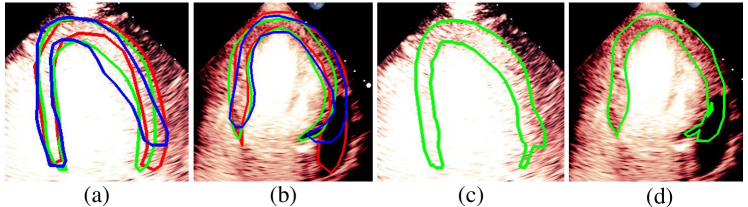

For variations caused by low quality images such as those of low resolution or significant artifacts, however, the unique ground truth may not be available. Take the myocardial segmentation task of Myocardial Contrast Echocardiography (MCE) as an example. An inter-observer experiment was conducted among five experienced cardiologists, and Fig. 1(a)(b) visualize the annotations of two images from three of these cardiologists. It can be seen that the labels by different cardiologists vary significantly, especially in locations where the intensity information of myocardium is very similar to the background. Table 1 shows the average Dice of the annotation of each cardiologist, using one of the others’ as the ground truth, over 180 images. We can observe that none of the Dice is above 0.9, some even under 0.8, confirming significant variations among the annotations. In this case, as the variations are caused by the image quality, even these cardiologists cannot tell which annotation is better than others, and a majority vote for ground truth would not make sense sometimes as can be seen in Fig. 1(c)(d). For this reason, we cannot obtain a unique ground truth in the evaluation process and the traditional metrics such as Dice and IoU cannot be used.

Visualization of myocardial segmentation from these methods is also shown in Fig. 4. We can see that for the Consensus, Confusion Matrix and Consistency methods, some unregulated shapes or discontinuity exist because the model cannot discriminate the actual myocardial from the artifacts which have the same intensity and texture information. However, the results of our method can alleviate the problem and accurately segment myocardium in MCE images.